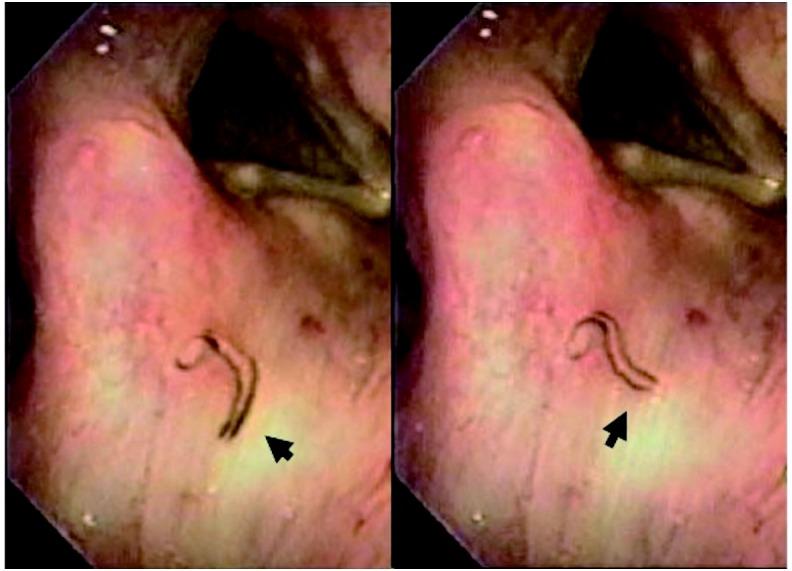

A 64-year-old Japanese man visited our outpatient department complaining of an irritable sensation in the throat, occurring two days after eating raw freshwater fish (carp sashimi) at a Japanese-style inn. During laryngeal endoscopy, a slow-moving worm (fluke) was found attached to the surface of the right aryepiglottic fold. After inhalation of 4% lidocaine, the fluke was removed using endoscopic forceps. Patient's throat symptoms immediately improved. The worm was microscopically identified as Clinostomum complanatum. C. complanatum is a digenetic trematode that usually infects fish-eating water birds. Clinostomum infections in humans are rare, and only 21 cases have been described in Japan and Korea. C. complanatum infection is known to occur after eating raw freshwater fish, which is a secondary intermediate host. In humans, the metacercariae are released into the stomach and migrate through the esophagus before lodging in the throat. Primary therapy involves endoscopic removal of the worm.

一名64岁的日本男性因在一家日式旅馆食用生淡水鱼(鲤鱼刺身)两天后出现喉咙不适感,前来我院门诊就诊。在喉镜检查时,发现一条活动缓慢的蠕虫(吸虫)附着在右侧杓会厌襞表面。吸入4%利多卡因后,用内镜钳将吸虫取出。患者的喉咙症状立即得到改善。经显微镜鉴定,该蠕虫为扁体 clinostomum。扁体 clinostomum 是一种双殖吸虫,通常感染食鱼水鸟。人类感染 clinostomum 极为罕见,在日本和韩国仅报道过21例。已知食用作为第二中间宿主的生淡水鱼后会发生扁体 clinostomum 感染。在人类中,囊蚴会释放到胃中,经食管迁移后寄居于喉咙。主要治疗方法是通过内镜取出蠕虫。